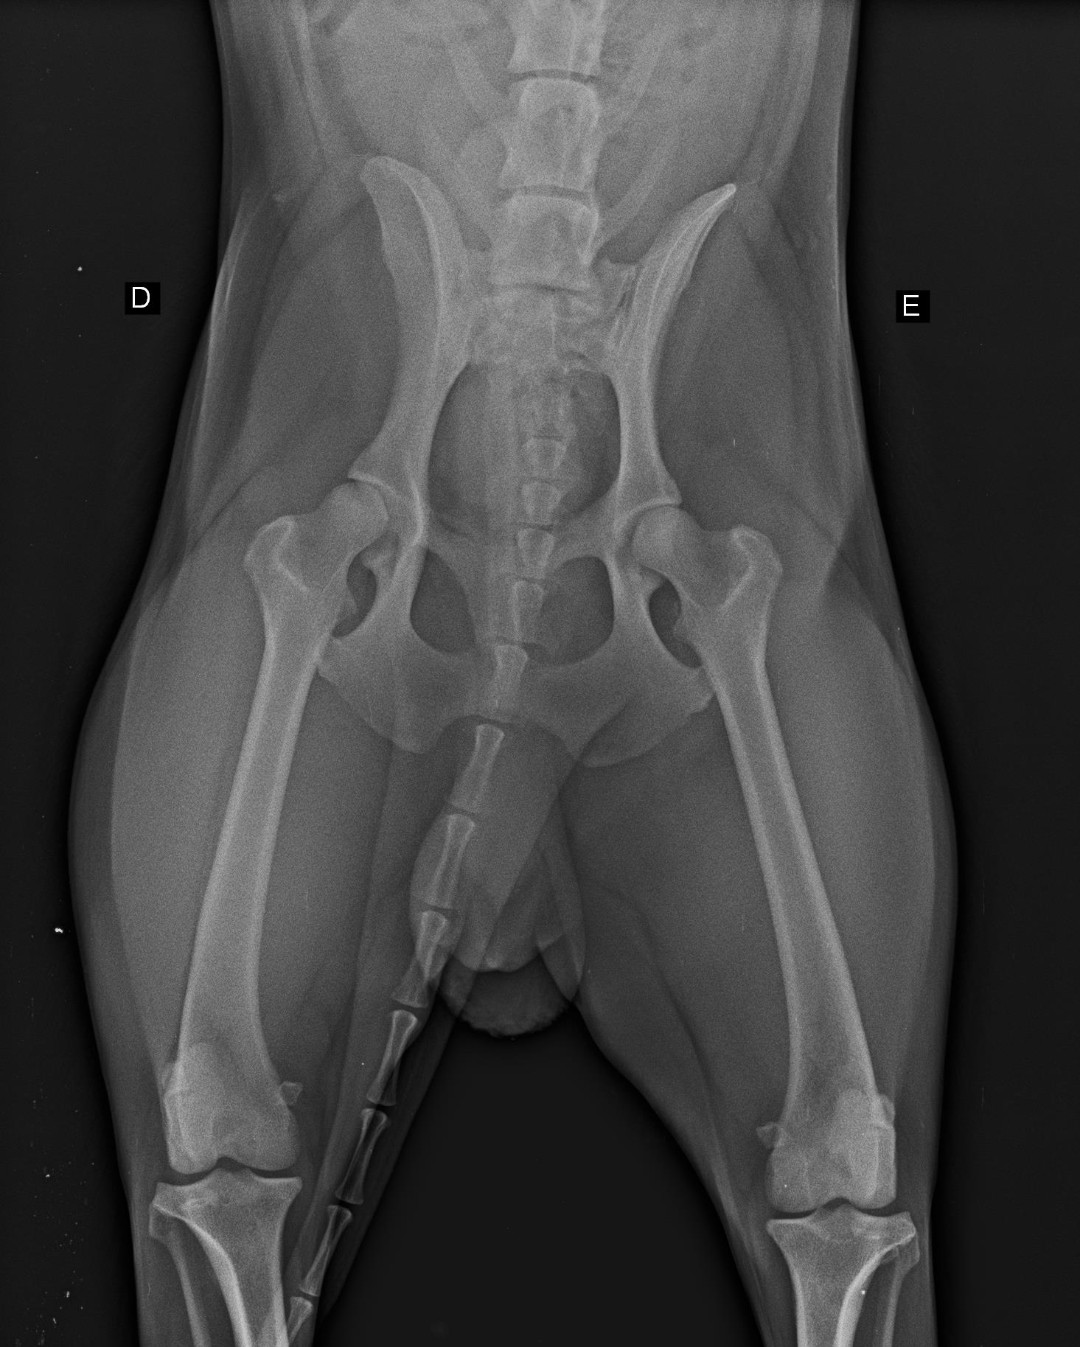

Raio X